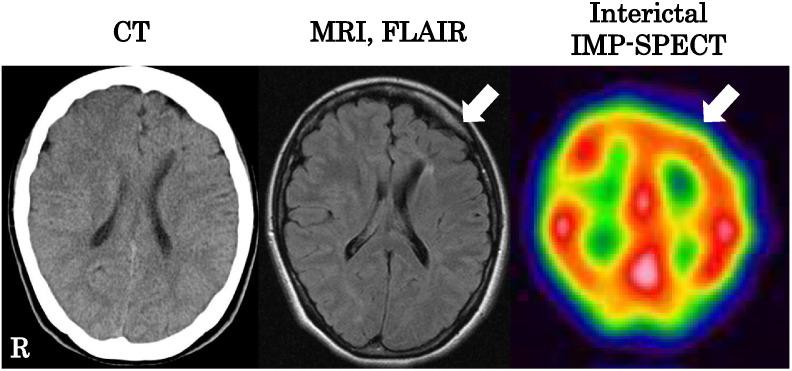

Tuberous sclerosis complex (TSC) is known to cause severe intractable epilepsy and mental retardation; however, diagnosis can be delayed in milder cases. We report a 26-year-old right-handed female patient who started having convulsions at age 7 days. She had several focal seizures per year that were intractable to treatment with carbamazepine or phenytoin. Her two sisters had several episodes of suspected epileptic seizures but had no symptoms related to TSC. Seizure semiology of the patient comprised of visual hallucination, loss of consciousness, and convulsive movements predominantly on the right. Physical examination revealed several small scattered angiofibromas over the nose that were histologically determined by skin biopsy. Hypomelanotic macules, shagreen patches, or periungual fibromas were not seen. Neurological examination showed mental retardation (MMSE: 23/30, WAIS-III: VIQ63, PIQ59, FIQ58) and decreased vibration sensation in both legs. Interictal EEG showed slow waves and epileptiform discharges broadly over the anterior quadrants bilaterally. Brain imaging showed multiple cortical tubers and malformation of cortical development but no subependymal nodules. Interictal IMP-SPECT showed hypoperfusion in the left frontal lobe. Cardiac rhabdomyoma was not noticed by cardiac echography. Truncal CT showed sclerosis of the bilateral lumbosacral joints. There was no abnormality in the lung, major arteries, liver, or kidneys. No hamartomas or retinal achromic patches were noticed by ophthalmologic evaluation. Administration of lamotrigine was effective for her seizures. This patient fulfilled two major features of diagnostic criteria for TSC and was diagnosed as definite TSC. Patients with mental retardation and epilepsy should be carefully evaluated for the possible diagnosis of TSC.